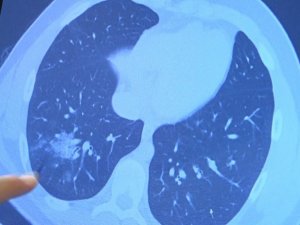

Aşı olmayan 14 yaşındaki çocukta ciddi akciğer tutulumları görüldü